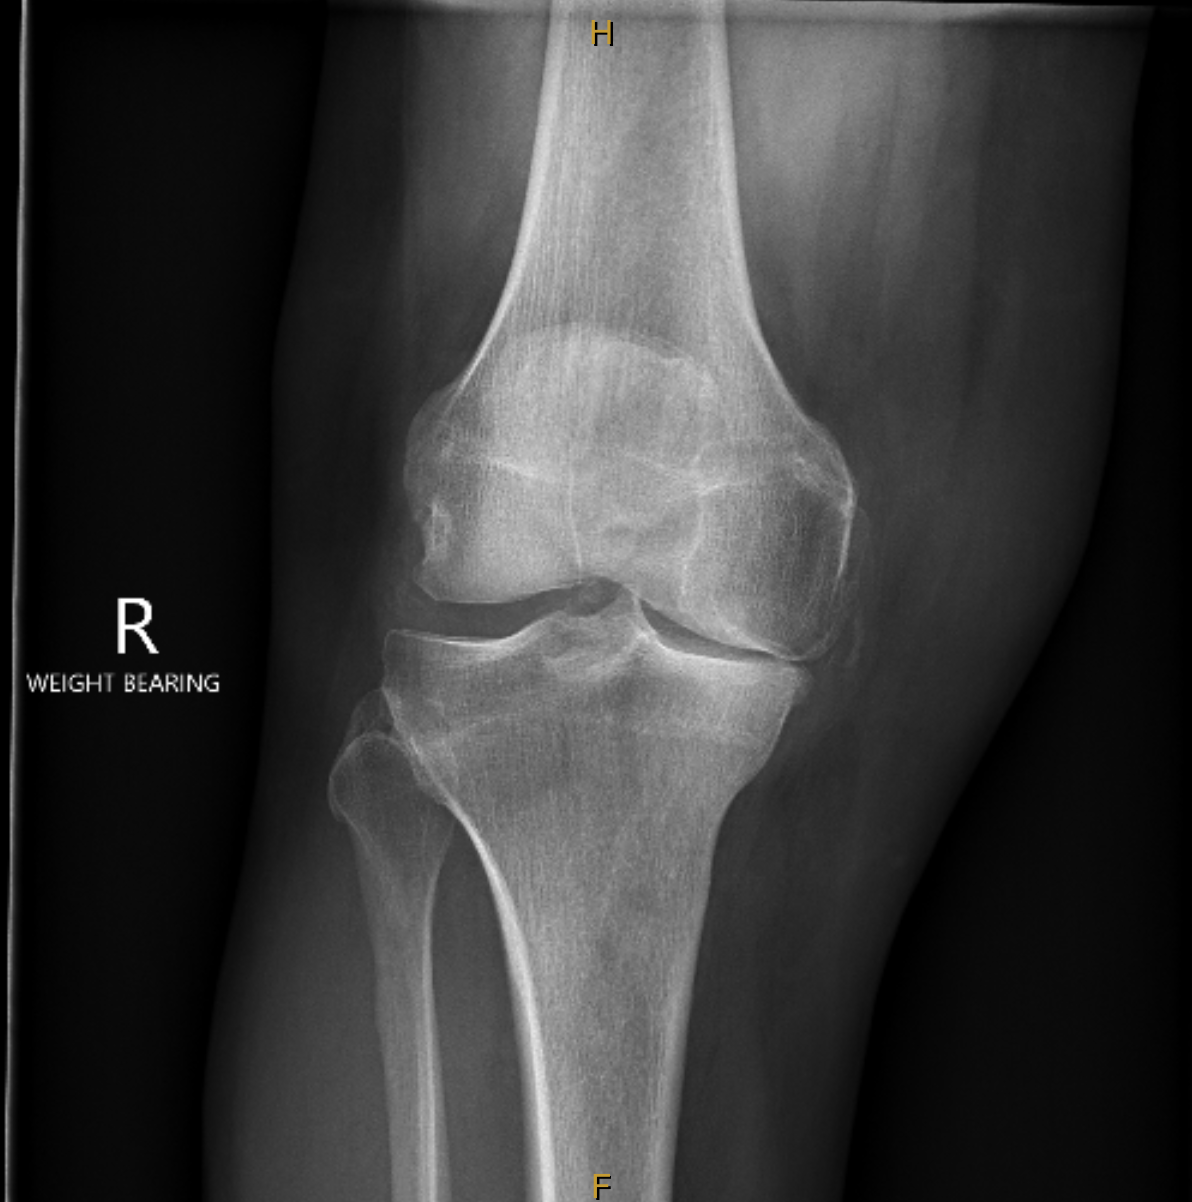

Knee Replacement

A knee replacement removes the worn cartilage and damaged joint surfaces of the knee and replaces them with smooth, durable artificial components. The new metal and plastic surfaces are designed to glide comfortably and restore stable movement.

It is considered when pain, stiffness, or loss of function from arthritis or certain knee injuries affects daily activities and non-surgical treatments are no longer providing relief.

The aims are to reduce pain, improve walking and knee function, and restore day-to-day comfort.

Modern knee implants provide reliable long-term performance. About 90 to 95 percent function well at 15 years, with durability affected by age, activity levels, and overall health.